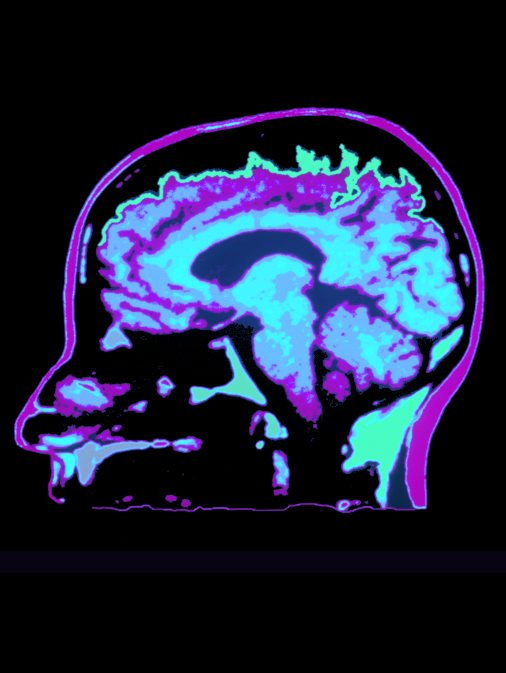

Фото: Custom Medical Stock Photo/Global Look Press

Исследование международной группы учёных выявило гендерные различия в появлении и развитии глиом (злокачественных опухолей мозга).

О результатах исследования пишет MedikForum. Учёные определили области в человеческом геноме, где опухоли мозга разных типов вызывают изменения. Таких областей оказалось три. Изменения в одной из них оказались более характерны для мужчин, в другой — для женщин. Ещё в одной области гендерных различий в целом не наблюдалось. Учёные считают, что дальнейшее изучение этих областей поможет создать генетические тесты, определяющие склонность к развитию опухолей мозга.

Риск развития глиомы у мужчин приблизительно на 50% выше, чем у женщин. Исследователи связывают это с женскими половыми гормонами и их защитной функцией. Показатели выживаемости также зависят от пола.

Во всём мире самый высокий уровень распространения глиом наблюдается в США, Канаде, Австралии и Северной Европе, что, по мнению учёных, говорит о связи опухолей с расой и этносом.